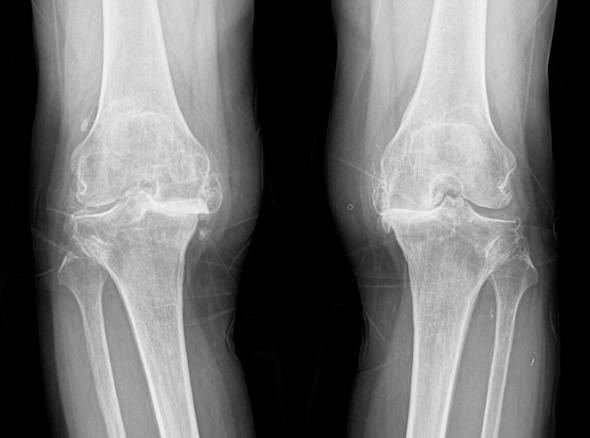

관절 마모 정도가 심하고 통증이 심한 환자분들은 재활치료나 약물만으로는 치료가 어려운 경우가 있습니다.

손상된 무릎 뼈를 제거하고, 그 부위에 특수 소재의 금속 재질로 구성된 인공관절을 삽입하는 수술을 시행할 수 있습니다.

관절연골이 망가져 쓸 수 없을 때 관절기능 회복을 위해 시행하며, 인공관절의 수명은 20~30년 정도 됩니다.

퇴행성관절염은 치료의 시기가 매우 중요합니다.

한번 진행이 시작되면 피하기가 어려워 치료가 빠를수록 진행을 최대한 늦출 수 있습니다.

말기의 퇴행성 관절염 환자에게 인공관절 수술은 최후의 수단으로 시행됩니다.